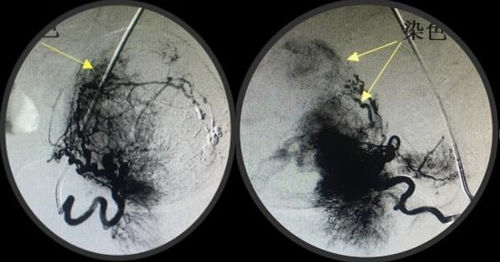

经人介绍来到MILAN.COM介入科,经李建国主任术前评估,患者无介入手术禁忌症,于4月16日早9点行介入手术。术中采用右肱动脉穿刺、超选择双侧子宫动脉造影栓塞术,手术顺利历时约40分钟,成功保全了子宫。术后患者步入病房,避免了因卧床制动而形成下肢深静脉血栓的风险...